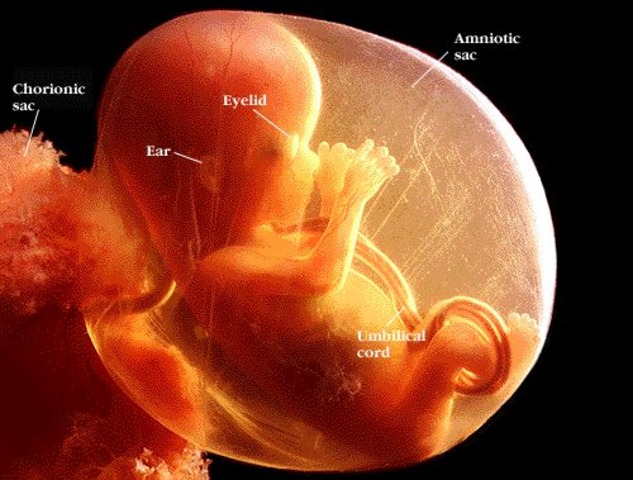

• 4 weeks

4 weeks

What's going on during the month : The amniotic sac, which will house your baby; the amniotic fluid, which will cushion her as she grows; and the yolk sac, which produces your baby's red blood cells and helps deliver nutrients to her until the placenta has developed and is ready to take over this duty.